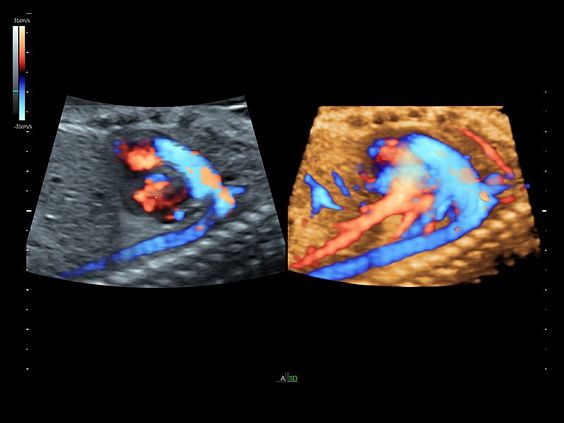

Клинические изображения

- Работа в В-, М-режимах, наличие импульсно-волнового, цветного допплеровского картирования, тканевого, энергетического и высокочувствительного направленного энергетического допплера (HD-Flow), тканевая гармоника

- Работа в В-, М-режимах, наличие импульсно-волнового, цветного допплеровского картирования, тканевого, энергетического и высокочувствительного направленного энергетического допплера (HD-Flow), тканевая гармоника

- B-Flow - режим недопплеровской визуализации кровотока.

- Усовершенствованное цветовое доплеровское картирование — для более детального исследования анатомии и функционального состояния сосудистой системы.